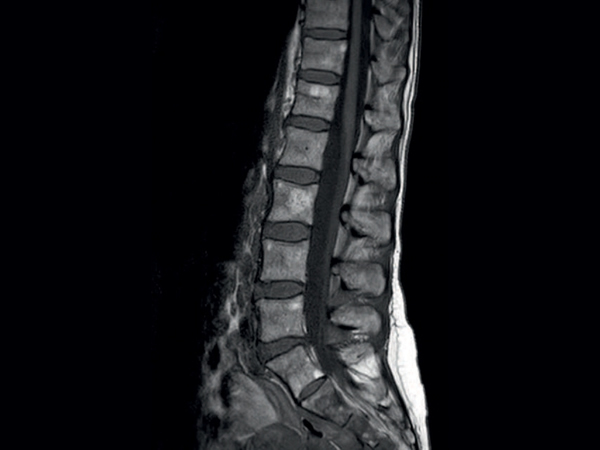

Comprehensive Lumbar Spine imaging at 1.5T

Meander Medical Center, Amersfoort, The Netherlands